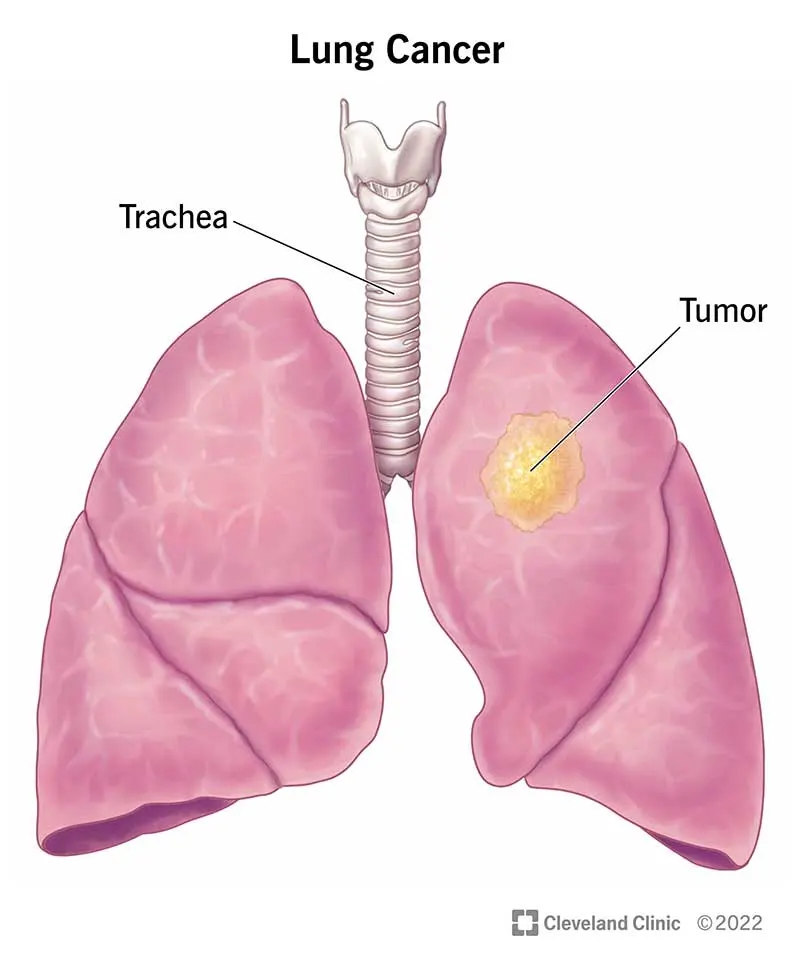

มะเร็งปอดคืออะไร และ PM2.5 เกี่ยวข้องอย่างไร?

มะเร็งปอดหลักๆ มี 2 ชนิด คือ ชนิดเซลล์เล็ก (small cell) ที่รุนแรง และชนิดเซลล์ไม่เล็ก (non-small cell) ที่พบได้บ่อยกว่า โดยเฉพาะในผู้หญิง การศึกษาในไต้หวันชี้ให้เห็นว่า ผู้หญิงในเอเชียตะวันออกมีแนวโน้มป่วยเป็นมะเร็งปอดเพิ่มขึ้นอย่างมีนัยสำคัญ โดยเฉพาะในจีนและเกาหลีเหนือ ซึ่งนักวิจัยเชื่อว่าเชื่อมโยงกับมลภาวะทางอากาศอย่าง PM2.5

ชนิดย่อยที่พบบ่อยที่สุดของมะเร็งปอดชนิดเซลล์ไม่เล็กคือ adenocarcinoma ซึ่งสัมพันธ์กับการกลายพันธุ์ของยีน EGFR ที่อยู่บริเวณถุงลม เมื่อยีนนี้ถูกกระตุ้นจาก PM2.5 ซ้ำๆ อาจทำให้เซลล์ถุงลมกลายสภาพเป็นเซลล์มะเร็งได้ นี่คือสิ่งที่ทำให้ผู้หญิงที่ไม่สูบบุหรี่ แต่ต้องเผชิญกับ PM2.5 มีความเสี่ยงเพิ่มขึ้น